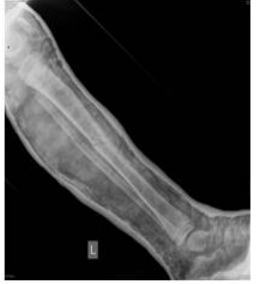

Figure 4&5: Tibial fracture with dislocation.

Figure 6: Control X-ray after conservative immobilization treatment.